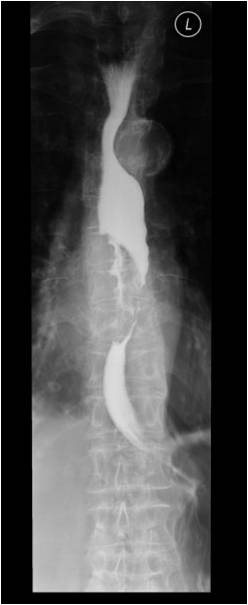

Image

Fig.5.: Epiphrenic diveticulum

Radiographic findings: Pulsion type epiphrenic diverticula manifest as rounded contrast retaining objects, with sharp contours. Pulsion diverticula characteristically have a narrow orifice.